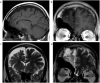

Dyke-Davidoff-Masson syndrome (DDMS) was first described in 1933 as a cerebral condition of hemispheric atrophy characterized clinically by contralateral hemiparesis, facial-asymmetry, seizures, and mental retardation. Neuroimaging findings include asymmetric thickening of the calvarium and enlargement of frontal and ethmoid sinuses. There have been 21 reported cases described in the literature with the syndrome undiagnosed until adult age, likely due to less severe or absent clinical findings or symptoms as described in the case presented in this report. This article describes a case where the Dyke-Davidoff-Masson imaging features were identified as an incidental finding on a CT scan of the brain performed for non-seizure related symptoms. A 54-year-old woman presented with weakness and gait difficulty and only upon further evaluation was she found to have cranial deformities. CT and MRI demonstrate encephalomalacia in the right frontal lobe anteriorly with gliosis and moderate unilateral cerebral atrophy, and extensive hypertrophy of the right frontal calvarium, right ethmoid cells and frontal sinuses.